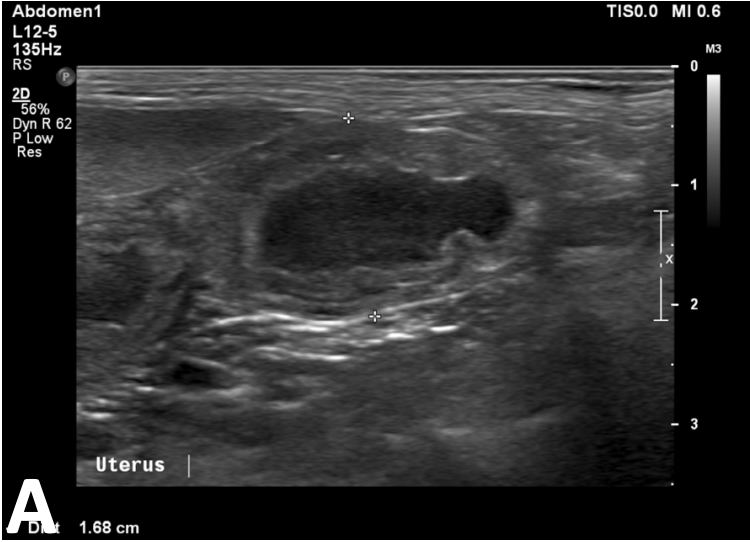

What is shown in this image?

A

hydrometra or mucometra